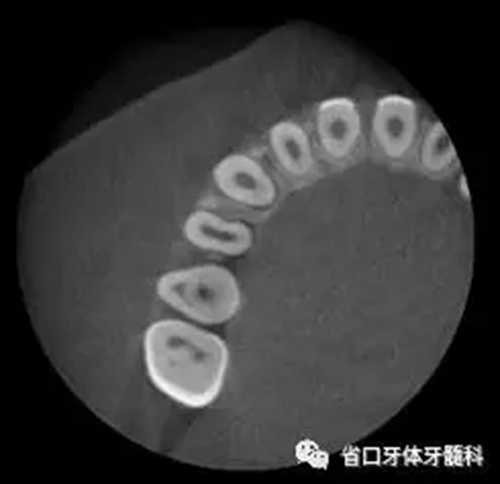

圖3 CBCT(2016-11-13):15由髓腔至根管內(nèi)見團塊阻射影像,阻射影中央為透射影,根尖1/3處見根管膨大,腭側(cè)牙槽骨破壞,根尖周低密度影范圍大,上頜竇黏膜增厚。